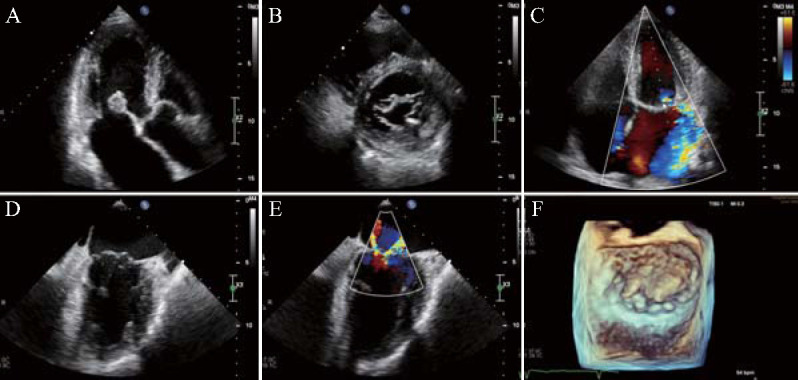

A 91-year-old male patient was admitted with a history of mitral valve prolapse diagnosed by physical examination ten years prior and recent onset of exertional chest discomfort persisting for over one month. Transthoracic echocardiography showed that the anterior leaflet of mitral valve was thickened and prolapsed with severe regurgitation, and transesophageal echocardiography further confirmed that the anterior and posterior leaflets of mitral valve were prolapsed with massive regurgitation (A1, A2, A3, P1 and P2 were all prolapsed). Thus, the diagnosis of Barlow syndrome was considered. Transcatheter edge-to-edge mitral repair was performed with two MitraClipTM G4 XTWs. After a 10 months follow-up, the patient's cardiac function was significantly improved, and the degree of mitral regurgitation was mild.

患者男,91岁,疑有Barlow病病史,体检诊断为二尖瓣脱垂10余年,运动后胸闷1个多月。经胸超声心动图显示二尖瓣前小叶增厚脱垂伴严重反流,经食管超声心动图进一步证实二尖瓣前、后小叶脱垂伴大量反流(A1、A2、A3、P1、P2均脱垂)。经导管二尖瓣边缘到边缘修复用两个Mitraclip XTWs。随访3个月,患者心功能明显改善,二尖瓣返流程度轻度。